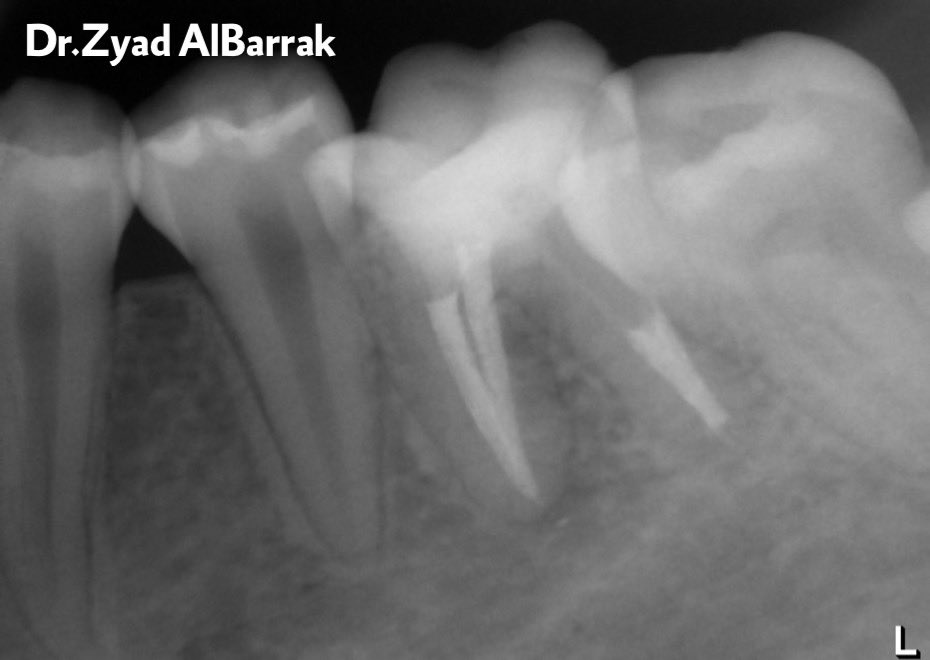

Causes of failure of initial endodontic therapy:

➢Poor cleaning and obturation

➢Coronal leakage

➢Untreated canals

➢Poor access cavity

➢Complications of instrumentation

➢Overextension of root canal filling

➢Persistent intracanal or extracanal infection

➢Radicular cyst